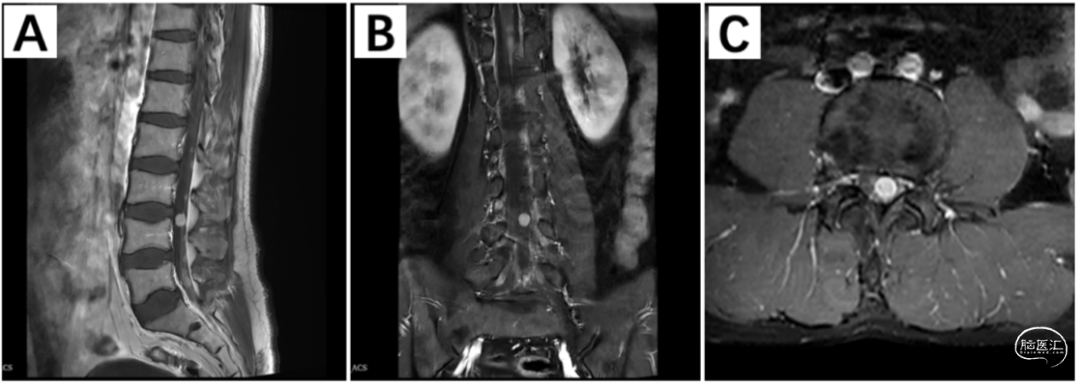

入院后查磁共振显示:胸腰段多发大小不等长T1短T2信号结节影,边界尚清,增强可见明显强化。其中,平胸8和腰3节段的两个占位较大,脊髓受压明显(图1)。

排除手术禁忌,提交科室讨论,患者以双下肢麻木起病,症状进展较快,MRI提示椎管内多发占位。首先考虑恶性转移瘤,胸8和腰3占位为症状责任病灶。手术指征明确,拟一期进行胸8-10全椎板硬膜下肿瘤切除术+腰3-4脊柱微创通道下硬膜内肿瘤切除术,送病理检查明确性质。